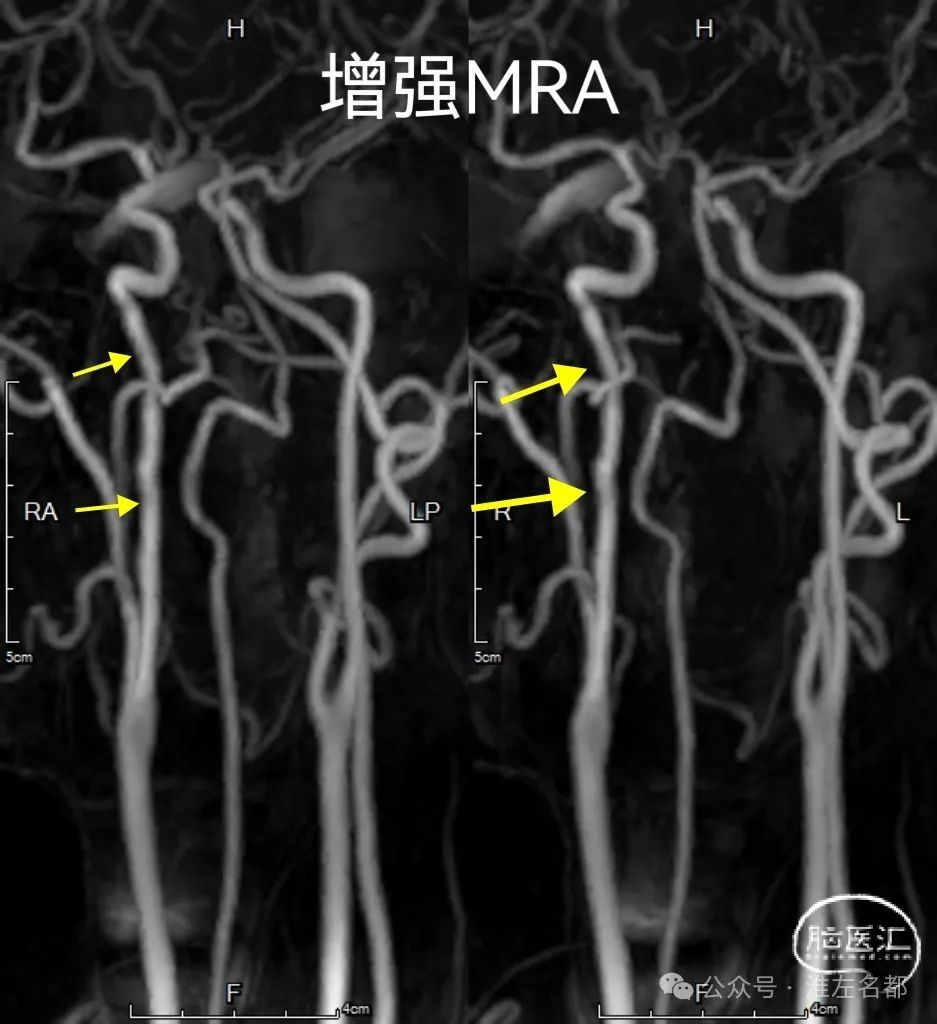

2024-3-24 复查

3D-TOF-MRA和增强MRA:原右侧C1夹层极重度狭窄管腔已获得明显缓解,局部管腔不规则,或轻度狭窄。3D-TOF-MRA上壁内血肿呈高信号。

3D-TOF-MRA和增强MRA:原右侧C1夹层处管腔恢复正常。